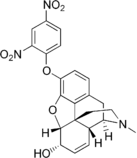

Opium alkaloids and derivatives

Phenanthrenes naturally occurring in (opium):

Semi-synthetic alkaloid derivatives

- Etorphine

- Etorphine